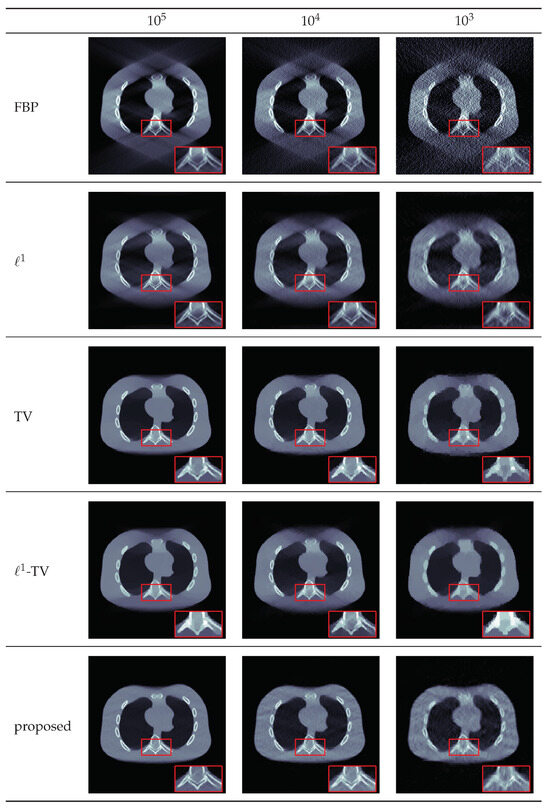

4.3. Results for Sparse View Data

| # Photons | Method | PSNR | SSIM |

|---|---|---|---|

| FBP | 20.8702 | 0.1767 | |

| 29.7290 | 0.7308 | ||

| TV | 30.3933 | 0.9294 | |

| -TV | 32.0445 | 0.8884 | |

| proposed | 31.0289 | 0.9302 |